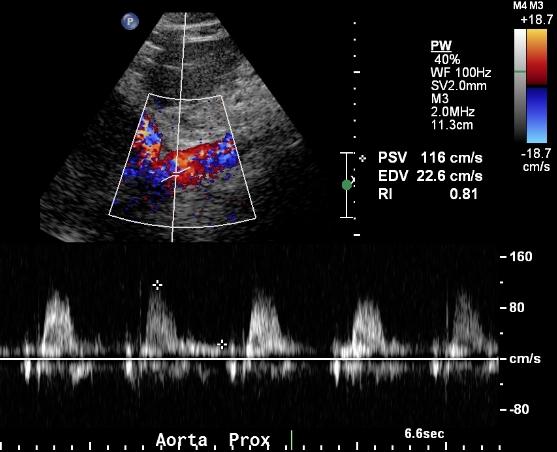

The midline approach is ideal for obtaining blood flow velocity in the proximal aorta. This velocity is later used to calculate the renal to aorta flow ratio. An increased ratio suggests significant renal artery stenosis. The velocity in the proximal aorta should be measured at the level of the origin of the superior mesenteric artery. The superior mesenteric artery is often easier to identify when the aorta is elongated as its course is often parallel to that of the aorta. Sampling of the superior mesenteric artery waveform should show a high resistant waveform, if the patient has indeed fasted.

Tip: the superior mesenteric artery waveform is usually higher velocity than the aorta. Choose to locate the pulse-wave cursor slightly proximal or distal to the superior mesenteric artery origin to avoid overlap between waveforms.